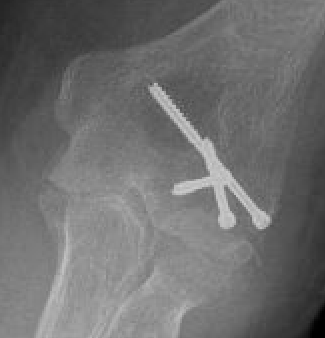

Fixation

Headless compression screws AP / PA

Posterolateral plate

Lateral approach and ORIF

Usually AP headless compression screws (violates articular surface)

- +/- PA screws (risk AVN)

- +/- excise isolated cartilage lesions

- +/- postero-lateral plate

ORIF with AP screws

ORIF Type II with screws